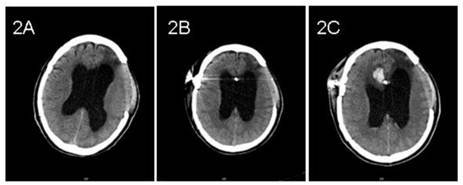

Case 2: A 58-year-old male underwent a decompressive left frontotemporal craniectomy and right frontotemporal craniotomy for traumatic intracerebral hematoma sustained during a motor vehicle collision 3 months previously. CT showed hydrocephalus with interstitial edema capping the frontal horns of the lateral ventricles (Figure 2A). Preoperative neurological examination was unremarkable. A VP shunt was placed with a Medtronic Strata Programmable Valve System (pressure level, 1.5). A ventricular catheter was inserted into the anterior horn of the right lateral ventricle at the first attempt. Twenty-four hours after surgery, CT imaging was normal and the pressure of the left decompressive window decreased (Figure 2B). On postoperative day 3, the pressure increased and the patient deteriorated. Emergent CT demonstrated hemorrhage along the path of the ventricular catheter and in both lateral ventricles (Figure 2C). The patient was treated conservatively and recovered gradually with a patent shunt tube.

Figure 2

Pre- and post- operative CT imaging of case 2. 2A: Preoperative CT showed hydrocephalus. 2B: Routine CT showed no evidence of hemorrhage on postoperative day 1. 2C: CT showed hemorrhage along the path of ventricular catheter on postoperative day 3.